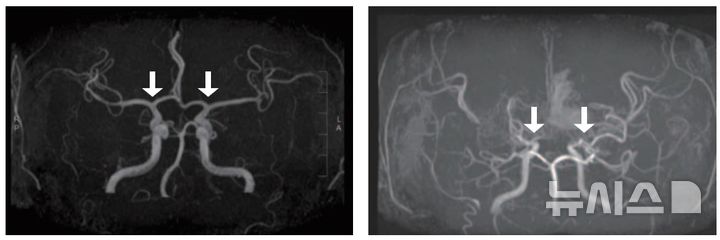

[서울=뉴시스] 류난영 기자 = 희귀난치성 뇌혈관질환 '소아 모야모야병'의 발생 양상과 치료 및 예후를 전국 단위로 분석한 결과가 나왔다...